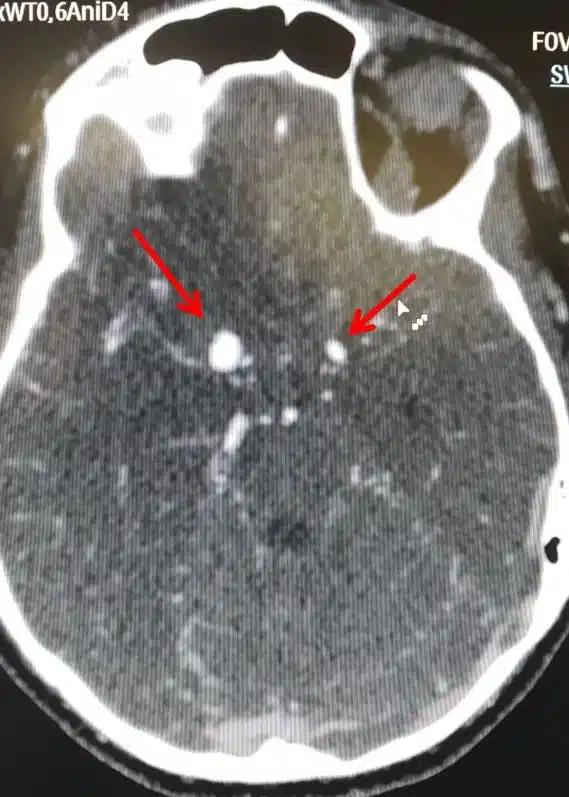

Ένα ανεύρυσμα εγκεφάλου είναι ένα εξόγκωμα ή διόγκωση σε ένα αιμοφόρο αγγείο στον εγκέφαλο.

Το ανεύρυσμα εγεκφάλου μπορεί να παρουσιάσει διαρροή ή ρήξη, προκαλώντας αιμορραγία στον εγκέφαλο (αιμορραγικό εγκεφαλικό επεισόδιο). Πιο συχνά μια ρήξη ανευρύσματος εγκεφάλου εμφανίζεται στο χώρο μεταξύ του εγκεφάλου και των λεπτών ιστών που καλύπτουν τον εγκέφαλο. Αυτό το είδος αιμορραγικού εγκεφαλικού επεισοδίου ονομάζεται “υπαραχνοειδής αιμορραγία”.

Υπάρχουν δύο μορφές εγκεφαλικών ανευρυσμάτων, το σακοειδές και το ατρακτοειδές ανεύρυσμα.

Η συχνότερη μορφή που μπορεί να πάρει ένα ανεύρυσμα είναι η ασκοειδής ή σακοειδής, δηλαδή σχηματίζεται στο αδύνατο σημείο της αρτηρίας ένας σάκος με μίσχο που τον ενώνει με την υπόλοιπη αρτηρία. Φαίνεται σαν ένα μούρο που προβάλλει από μια αρτηρία. Συνήθως αναπτύσσεται σε περιοχές διχασμού αγγείων.

Εκτιμάται ότι 3,5% έως 6% του γενικού πληθυσμού έχουν σακοειδές ανεύρυσμα. Στο 15% έως 30% των περιπτώσεων αυτών, υπάρχουν περισσότερα από ένα σακοειδή ανευρύσματα.